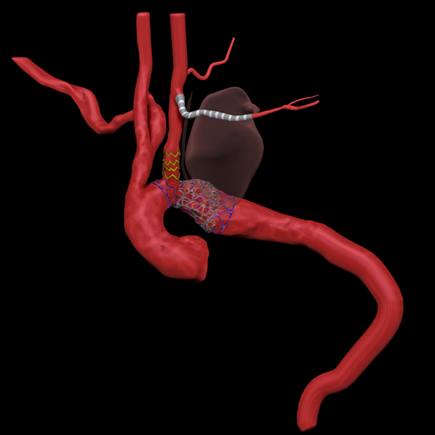

第三步、经鞘内输送Gore TGU262610覆膜支架至无名动脉后缘释放。

第四步、经左颈总动脉穿刺针破膜原位开窗,球囊逐步扩大窗口,确保左颈总动脉血供。考虑还需要植入CP支架,先在左颈总留置导丝并不植入小支架。

第五步、 通过Gore 大鞘内导入NUMED CVRDCP8Z39球扩支架,定位于主动脉弓部缩窄部位释放。然后在左颈总动脉植入Fluency 12*40,球囊后扩。

第六步、结扎左锁骨下动脉近心端,采用Gore-Tex 6mm人工血管行左颈总动脉-左锁骨下动脉旁路移植,左椎动脉近端结扎,远端端侧吻合于左颈总动脉。

术后复查3D图